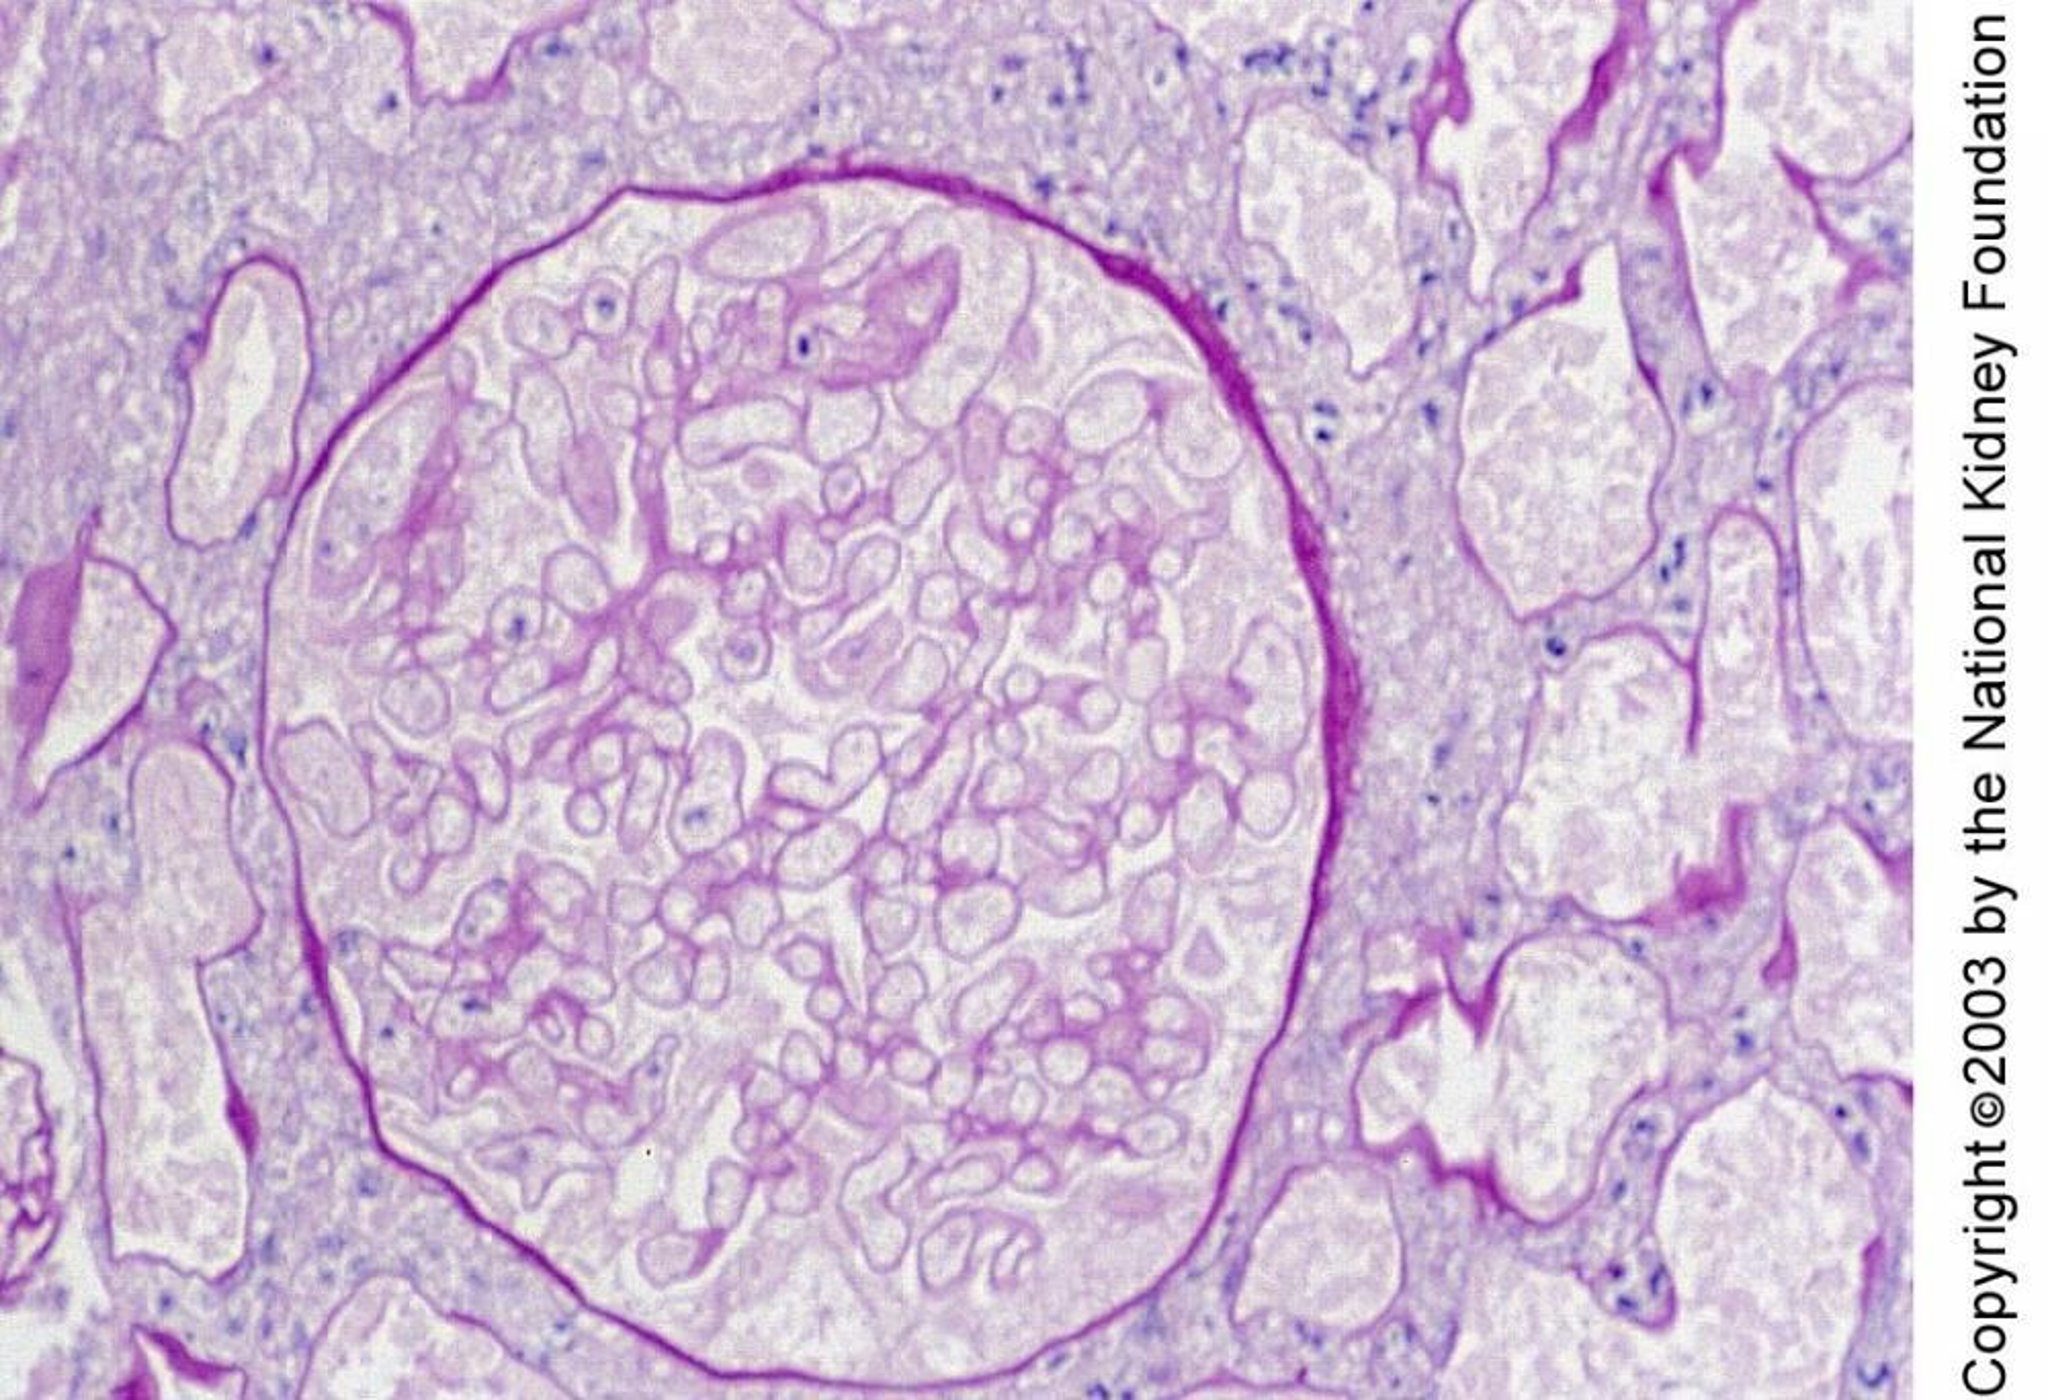

Hoại tử vỏ thận

Hoại tử vỏ thận được đặc trưng mô học bởi hoại tử cầu thận và ống thận. Hoại tử trong mẫu sinh thiết này biểu hiện bằng các nhân nhỏ và các đường viền giống như bóng ma của tế bào (nhuộm axit-Schiff định kỳ, × 400).

Hình ảnh do bác sĩ Agnes Fogo và American Journal of Kidney Diseases' Atlas of Renal Pathology cung cấp (xem www.ajkd.org).